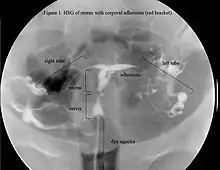

The history of a pregnancy event followed by a D&C leading to secondary amenorrhea or hypomenorrhea is typical. Hysteroscopy is the gold standard for diagnosis.[18] Imaging by sonohysterography or hysterosalpingography will reveal the extent of the scar formation. Ultrasound is not a reliable method of diagnosing Asherman's Syndrome. Hormone studies show normal levels consistent with reproductive function.

In an attempts to estimate the prevalence of AS in the general population, it was found in 1.5% of women undergoing hysterosalpingography HSG,[50] and between 5 and 39% of women with recurrent miscarriage.[51][52][53]